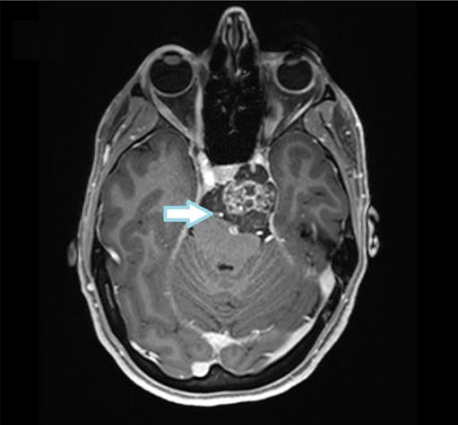

在近四年内,该患者于多家医院接受三次肿瘤切除手术(包括两...